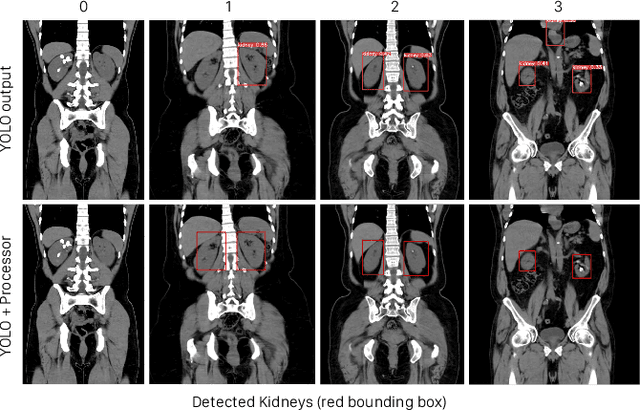

Abstract:Kidney stone disease results in millions of annual visits to emergency departments in the United States. Computed tomography (CT) scans serve as the standard imaging modality for efficient detection of kidney stones. Various approaches utilizing convolutional neural networks (CNNs) have been proposed to implement automatic diagnosis of kidney stones. However, there is a growing interest in employing fast and efficient CNNs on edge devices in clinical practice. In this paper, we propose a lightweight fusion framework for kidney detection and kidney stone diagnosis on coronal CT images. In our design, we aim to minimize the computational costs of training and inference while implementing an automated approach. The experimental results indicate that our framework can achieve competitive outcomes using only 8\% of the original training data. These results include an F1 score of 96\% and a False Negative (FN) error rate of 4\%. Additionally, the average detection time per CT image on a CPU is 0.62 seconds. Reproducibility: Framework implementation and models available on GitHub.